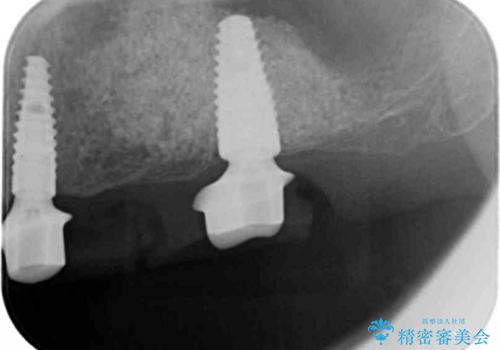

- 重度の虫歯により左上の歯を失い、インプラント治療は怖いため嫌厭して放置していたが、いよいよ食事に困りしっかりと噛めるようになりたいと希望され来院されました。

残存している小臼歯も虫歯が大きく保存が難しいため抜去を行い造骨を含めたインプラント治療を行います。

しっかりと造骨を行ったことでインプラント周囲には十分な量の骨が存在し安定したインプラント周囲環境を整えることができました。